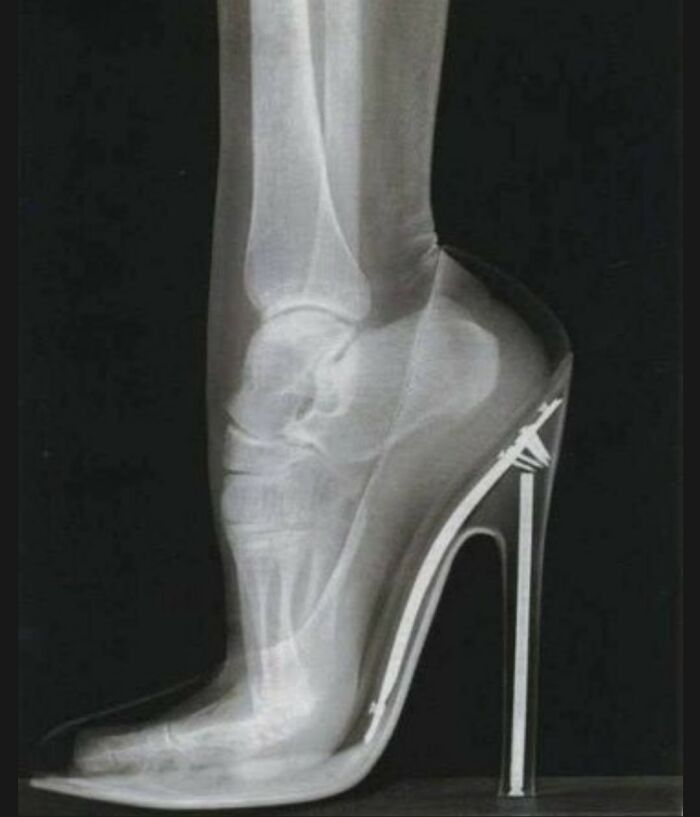

This X-ray shows the position of a foot when wearing a high-heeled shoe.

High heels may enhance a woman’s beauty, but human biology teaches us that the body is not adapted to this accessory. Therefore, overusing high heels can cause severe problems due to the improper biomechanical stress placed on the entire body.

Wearing high heels forces the foot to be on its toes for extended periods. This causes the muscles to adapt to this position with a shortened length, and in fact, muscle shortening of the triceps surae (gastrocnemius and soleus) and plantar muscles has been demonstrated as a result of this posture. In the long run, this can lead to pain in the back of the knee.